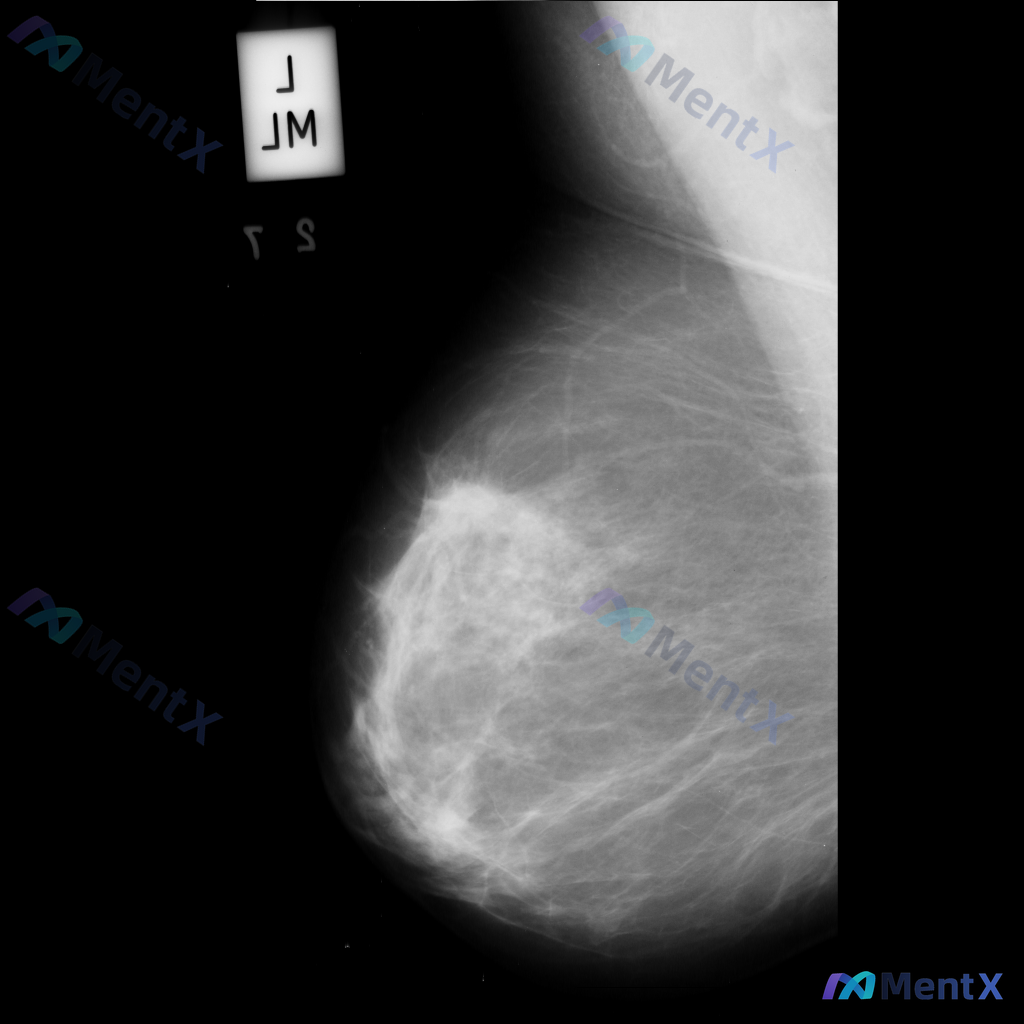

整理到一份乳腺钼靶的影像讨论资料,先和大家同步一下基本信息: - 检查部位:左乳 - 投照体位:内外斜位(MLO) - 影像表现: 1. 左乳外侧偏上象限可见不规则高密度肿块影 2. 肿块边缘模糊,部分区域有毛刺样改变 3. 肿块周围存在局限性结构扭曲 目前先不补充更多信息,想听听大家的第一判断:这...